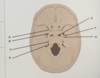

what is A

foramen retundum

what is B

foramen ovale

what is C

IAM

what is D

jugular foramen

what is E

foramen lacerum

what is F

foramen spinosum

what is G

carotid canal